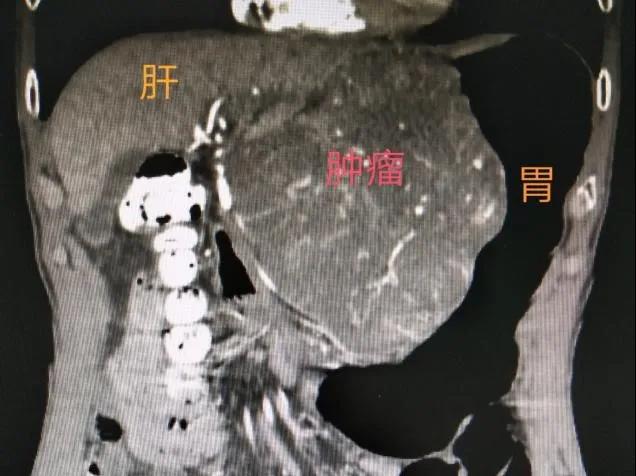

今年1月,李先生出现上腹隐痛不适,在当地县医院发现左上腹区占位性病变后,经人介绍来到桂林医学院第二附属医院胃肠外科住院治疗。经检查发现一个紧贴肝和腹膜后大血管、大小约152mm×128mm×78cm的肿块。胃肠外科副主任陈伟教授组织MDT讨论,认为胃巨大间质瘤可能性大,初步判断为原发不可切除型,此时如果勉强手术,可能术中大出血且行全胃甚至联合脏器切除可能性高,损伤代价太大,完整切除肿瘤的可能性也很小,如肿瘤破裂或残留则极易复发,治疗效果不佳。

2020-2-2转化治疗前CT示肿瘤巨大